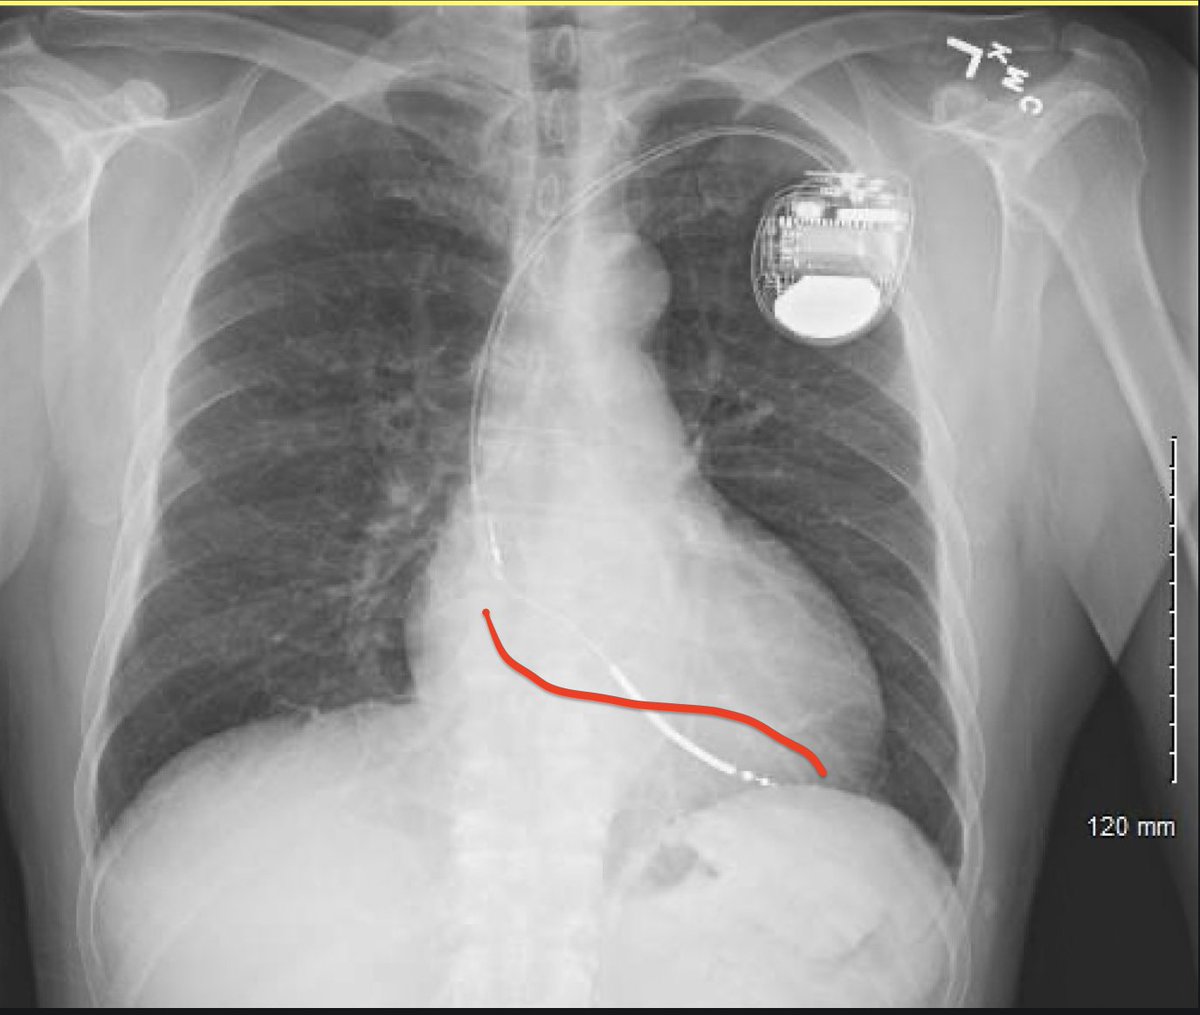

My concern — agree w others. Feared ICD lead crossed PFO into LV. This was next day CXR after new implant.

Findings — Lead in RV. All OK. Pt discharged home.

Also look in AP at the crossing point and contour at the TV. If it’s high up, like mine, maybe consider this is the PFO. In the image, I’ve drawn about where I’d have expected the TV crossing to be. Obviously, there is a lot of latitude here, and this lead was ultimately fine. Image

So, then, you are making rounds Saturday AM and see this CXR. What to do?

I did the implant. I was pretty darn sure I’d done all these careful steps. Even so, you gotta be certain. Is there any uncertainty? Sure.

We ordered the echo and all was well. Phew.